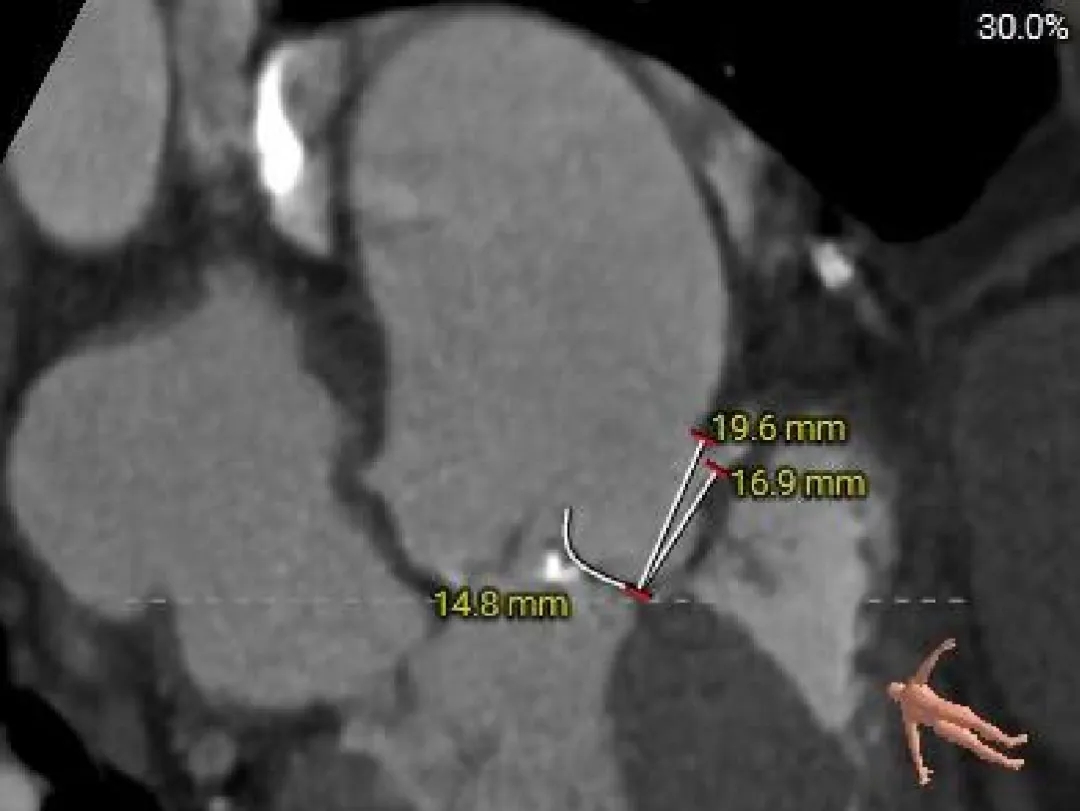

冠脉风险评估

Left Coronary

LCA & Leaflet

Right Coronary

RCA & Leaflet

左、右冠脉高度尚可

双侧瓣叶不长

结合SOV、STJ内径评估冠脉风险不高